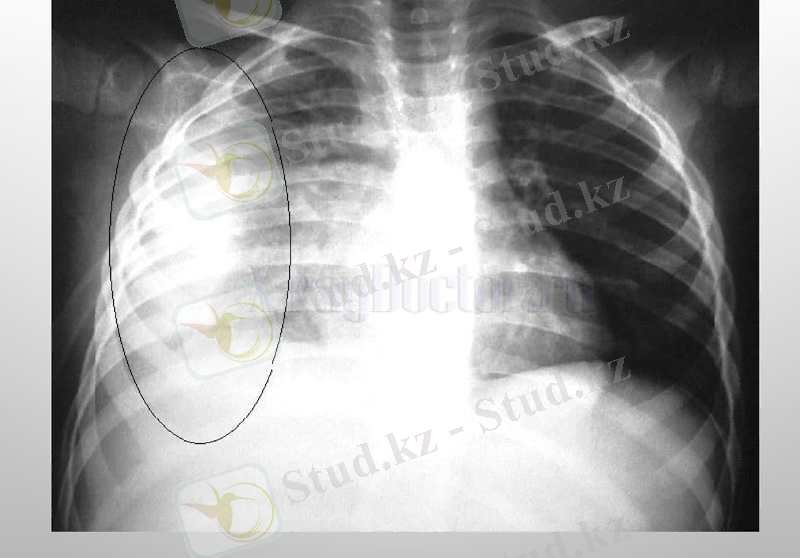

Плеврит - плевра қуысында сұйықтықтың жиналуы. Плевра - көкіректің ішкі бетін астарлап жататын сірі қабық.

Плевритті шартты түрде құрғақ (фибринозды) және іріңдік (экссудативті) деп бөледі. Құрғақ Плеврит кезінде сірлі қабық ісініп, қалыңдайды да қабыну процесі басталады. Ал іріңдік Плевритте плевра қуысы қан, ірің аралас сұйықтыққа толып кетеді. Адамда туберкулезді Плеврит жиі кездеседі. Плевриттің бұл түрі өкпеде немесе лимфа түйіндерінде басталып, кейін өкпені түгел қабындырады. Науқастың дене қызуы көтеріліп, құрғақ жөтел пайда болады.

Плевриттің диагностикасында рентгенография рентгеноскопии кеуде жасушаларының, плевральді қуыста УЗИ, плевральді пункции, диагностикалық торакоскопия жасалынады.

Туберкулезді плеврит